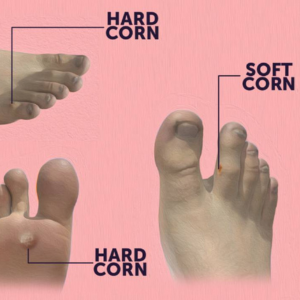

Corn Excision